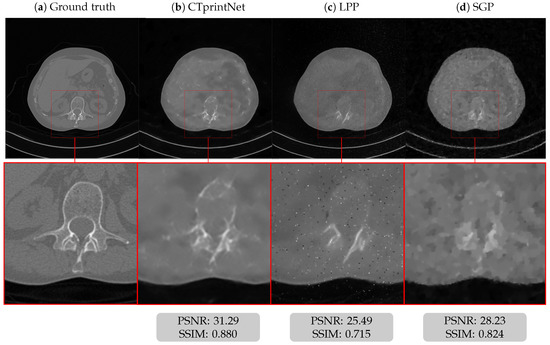

5.1. Results on a Synthetic Dataset

5.3. Results on a Realistic Dataset